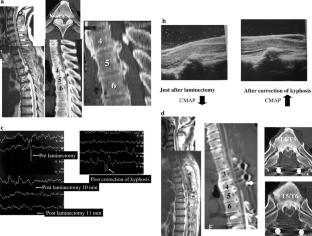

To investigation of the outcomes of indirect posterior decompression with corrective fusion for myelopathy associated with thoracic ossification of the longitudinal ligament, and prognostic factors. Conservative treatment for myelopathy associated with thoracic ossification of the longitudinal ligament (OPLL) is mostly ineffective, and treatment is necessary. However, many authors have reported poor surgical outcomes, and no standard surgical procedure has been established. We have been performing indirect spinal cord decompression by posterior laminectomy and simultaneous corrective fusion of the thoracic kyphosis. Twenty patients underwent indirect posterior decompression with corrective fusion, and were included in this study. The follow-up period was minimum 2 years and averaged 2 years and 9 months (2–5 years 6 months). Operative results were examined using JOA scoring system (full marks: 11 points) and Hirabayashi’s recovery rate, as excellent (100–75%), good (74–50%), fair (49–25%), unchanged (24–0%) and deteriorated (i.e., decrease in score less than 0%). Cases in which the spinal cord is floating from OPLL on intraoperative ultrasonography were defined as the floating (+) group, and those without floating as the floating (−) group. In addition, we used compound muscle action potentials (CMAP) as intraoperative spinal cord monitoring and the cases were divided into three groups: Group A, no change in potential; Group B, potential decreased, and Group C, potential improved. The mean pre- and postoperative JOA scores were 6.2 and 8.9 points, respectively, and the recovery rate was 56%. The outcome was rated excellent in three, good in eight, fair in six, unchanged in two, and deteriorated in one. The mean preoperative thoracic kyphosis measured 58°, and was corrected to 51° after surgery. On intraoperative ultrasonography, 12 cases were included in the floating (+) and 8 in the floating (−) groups; the recovery rates were 58 and 52%, respectively, showing no significant difference between the recovery rates of the two groups. Regarding intraoperative CMAP, the outcome was excellent in one, good in seven, fair in four, and unchanged in one in Group A; fair in one, unchanged in one, and deteriorated in one in Group B, and excellent in two and good in one in Group C. The recovery rates were 50, 48 and 68.3% in Groups A, B and C, respectively, showing that the postoperative outcome was significantly poorer in Group B. Although indirect posterior decompression with corrective fusion using instruments obtained satisfactory outcomes, not all cases achieved good outcomes using this procedure. We consider that additional application of anterior decompressive fusion is preferable when improvement of symptoms occurs not satisfactory after indirect posterior decompression with corrective fusion using instruments. Intraoperative spinal cord monitoring of CMAP demonstrated that the spinal cord was already impaired during the laminectomy via the posterior approach. Concomitant intraoperative monitoring of CMAP to avoid impairment of the vulnerable spinal cord and corrective posterior spinal fusion with indirect spinal cord decompression is recommendable as a method capable of preventing postoperative neurological aggravation.